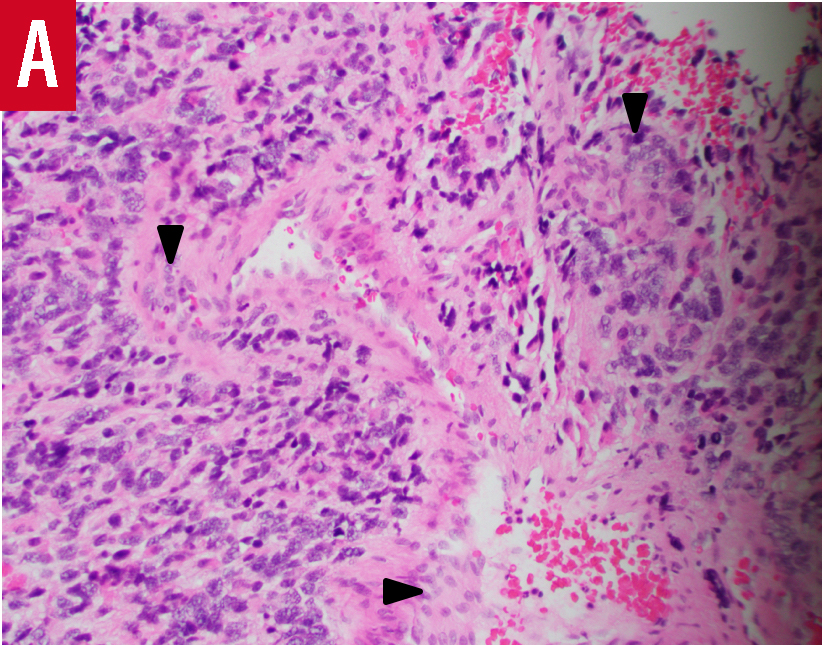

Pathology results of a biopsy specimen showed a densely cellular infiltrating malignant tumor with nuclear pleomorphism, a high mitotic rate with an elevated Ki-67 labeling index, and glomeruloid vascular proliferation. The tumor cells strongly expressed glial fibrillary acidic protein, indicating they were astrocytic in origin. The final pathologic diagnosis was glioblastoma, World Health Organization grade IV (Figure 2).

Figure 2. Biopsy sections showed histologic findings typical of glioblastoma, including hypercellularity, nuclear pleomorphism, vascular endothelial proliferation (arrowheads), and a mitotic figure (arrow) (hematoxylin-eosin, original magnification ×200 [panel A] and ×400 [panel B]).